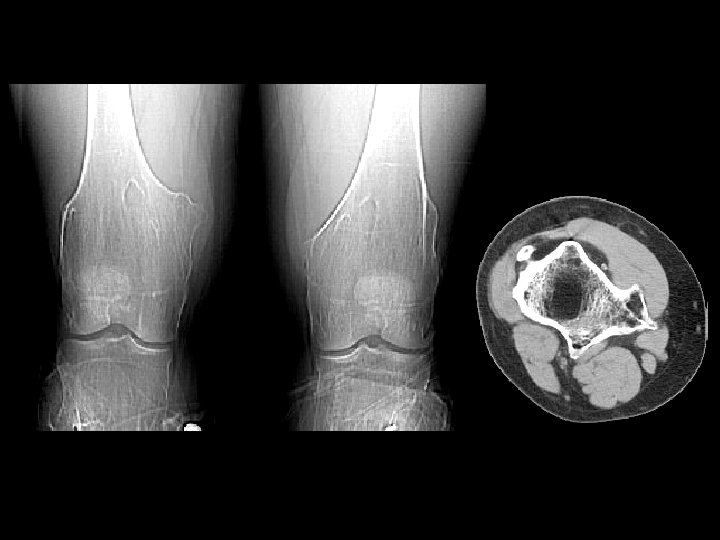

Rickets • Findings: – Cupped and frayed metaphyses – Wide physes (increased osteoid) – Long bone bowing – Decreased bone density • ddx: – NONE! – This is an Aunt Minnie!